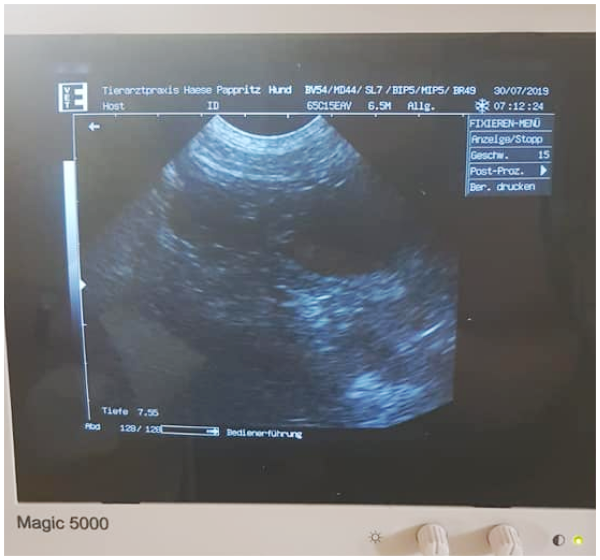

Unsere Gwendolin vom Rittergut wurde am 6. u. 7. Juli 2019 von Cid pod Svatou Horou gedeckt. Werte der Verpaarung: IK 0,00 und AVK 98,39

30. Juli 2019